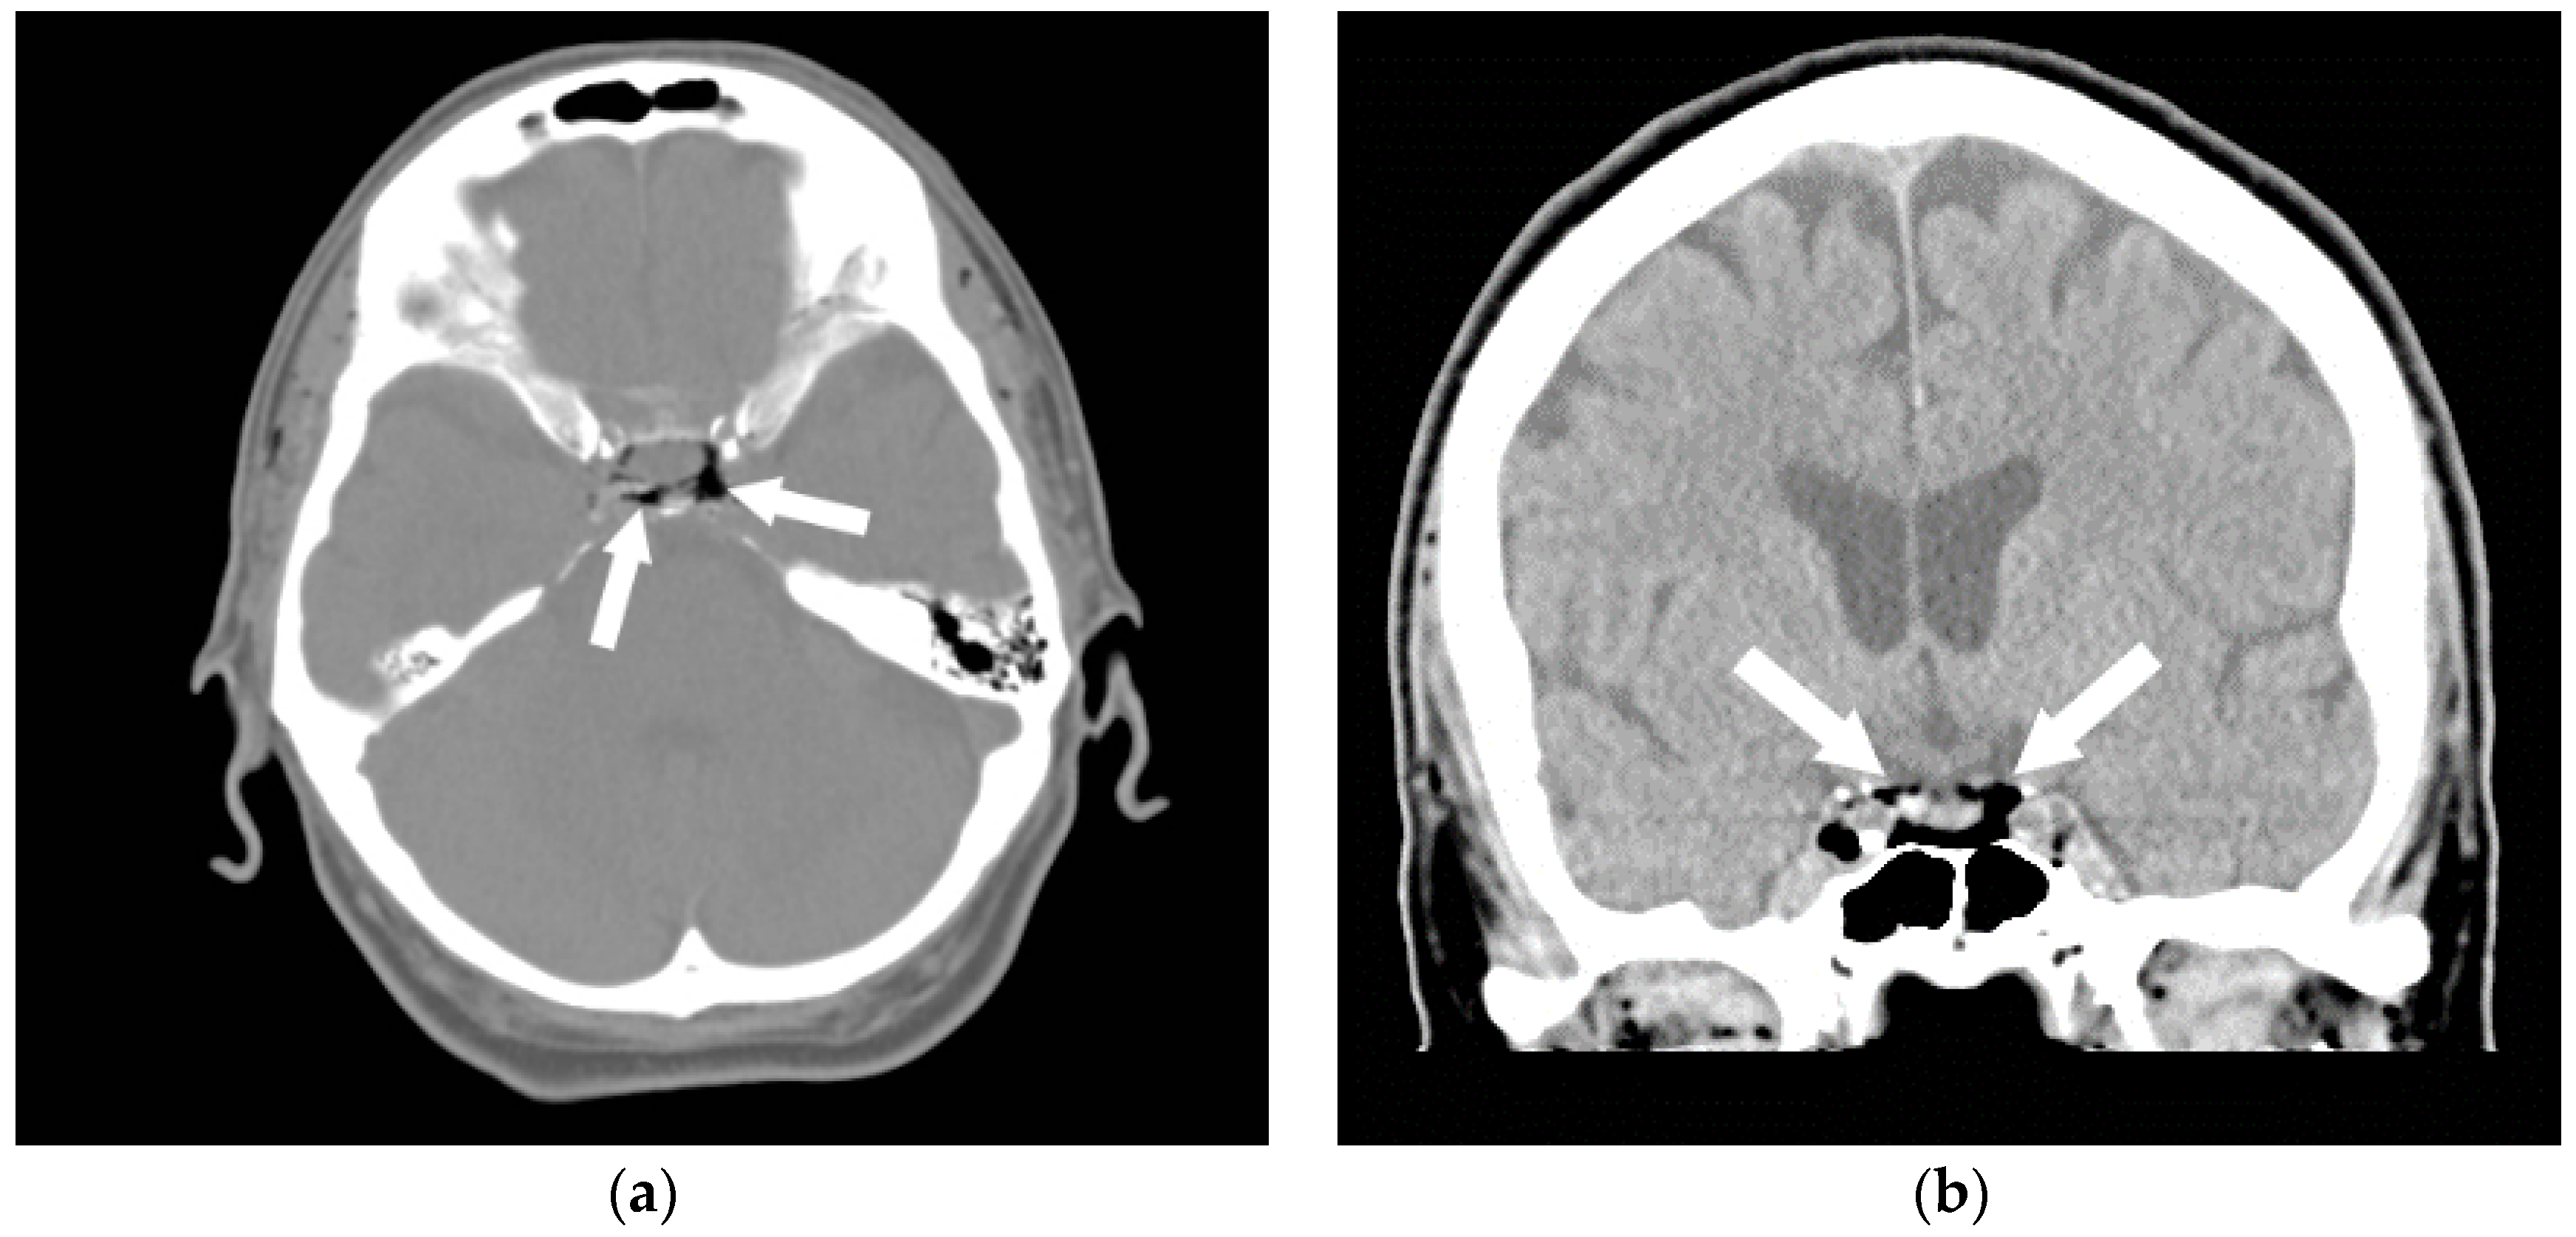

5. Air Embolism Management

5.1. Initial Management Techniques

5.2. Advanced Management